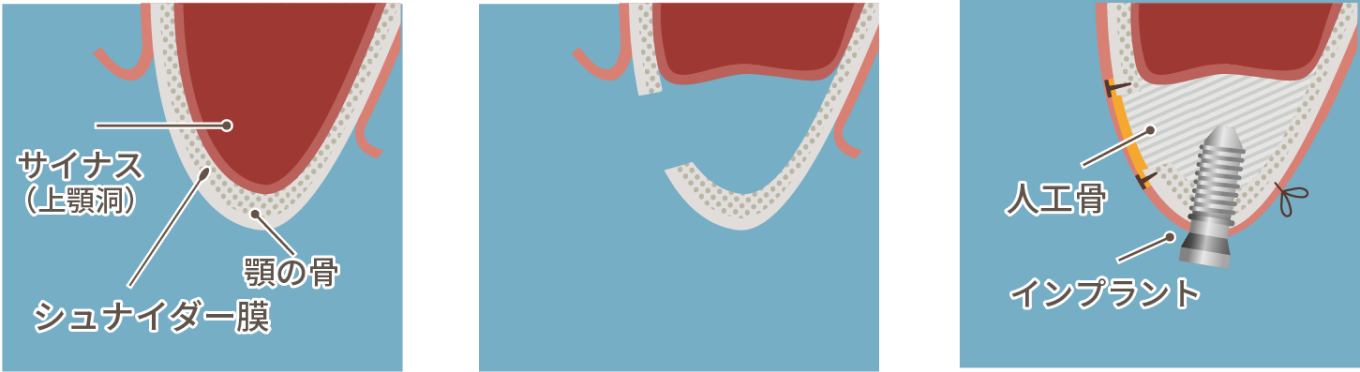

抜歯後、長期間放置したり、歯周病・破折による感染などにより骨が痩せてしまった場合、インプラントが難しくなることがあります。その場合、「骨造成」により骨の量を増やしインプラント体を埋め込むために必要な骨の厚みを確保します。ただし、移植する骨が多い場合や重篤な糖尿病などの全身疾患がある場合には処置が行えません。

骨造成には様々な術式があり、治療部位や残っている骨量によって、適した方法が異なっております。

上顎の骨造成法の一つで、頬側から上顎洞底を持ち上げて人工骨や自家骨を塡入する方法です。歯槽骨頂から上顎洞底までの距離が6mm以下の極度な骨量不足の場合に用いられます。ソケットリフト法よりも広い範囲の症例に適用できます。

上顎の骨造成法の一つで、インプラントを埋入する穴から上顎洞底部を持ち上げて人工骨や自家骨を塡入する方法です。歯槽骨頂から上顎洞底までの距離が7mm以下の中程度の骨量不足の場合に用いられます。